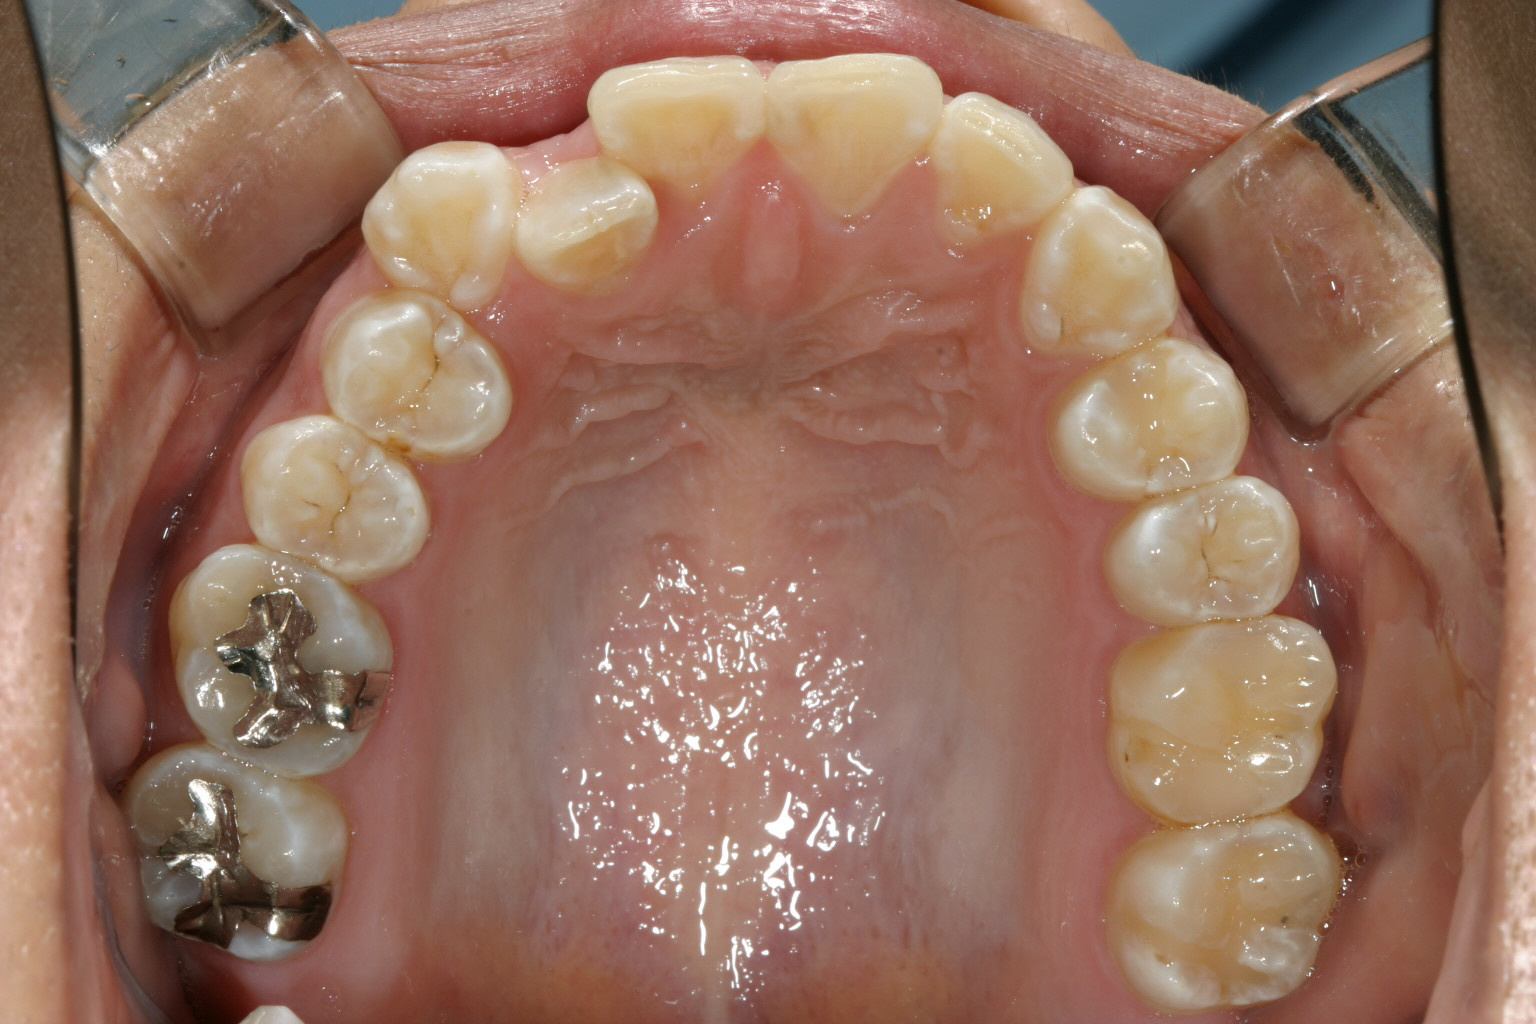

マルチループワイヤー使用で3ヵ月です。 もう殆ど犬歯の飛び出し改善してます。

下顎もマルチループワイヤーしています。

前から見るとこんな感じです。 ちょっと見栄え悪すぎですかね~